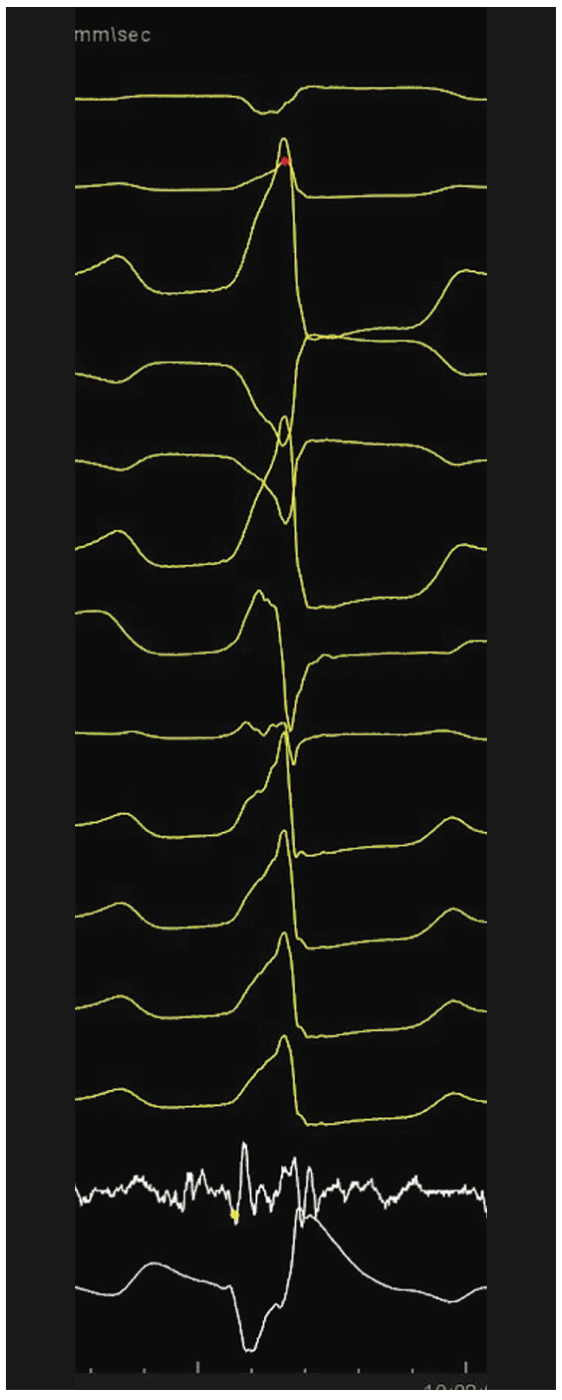

Videos 13a-b and Figure 13c demomstrate a zero fluoroscopic ischemic, incessant, hemodynamically tolerated VT ablation and creation of a 4-chamber EAM/sound map and a figure-of-8 VT in a patient with a large anteroapical infarction along with the electrogram resolution afforded by small 1-mm electrodes of the Pentaray in the isthmus corridor.